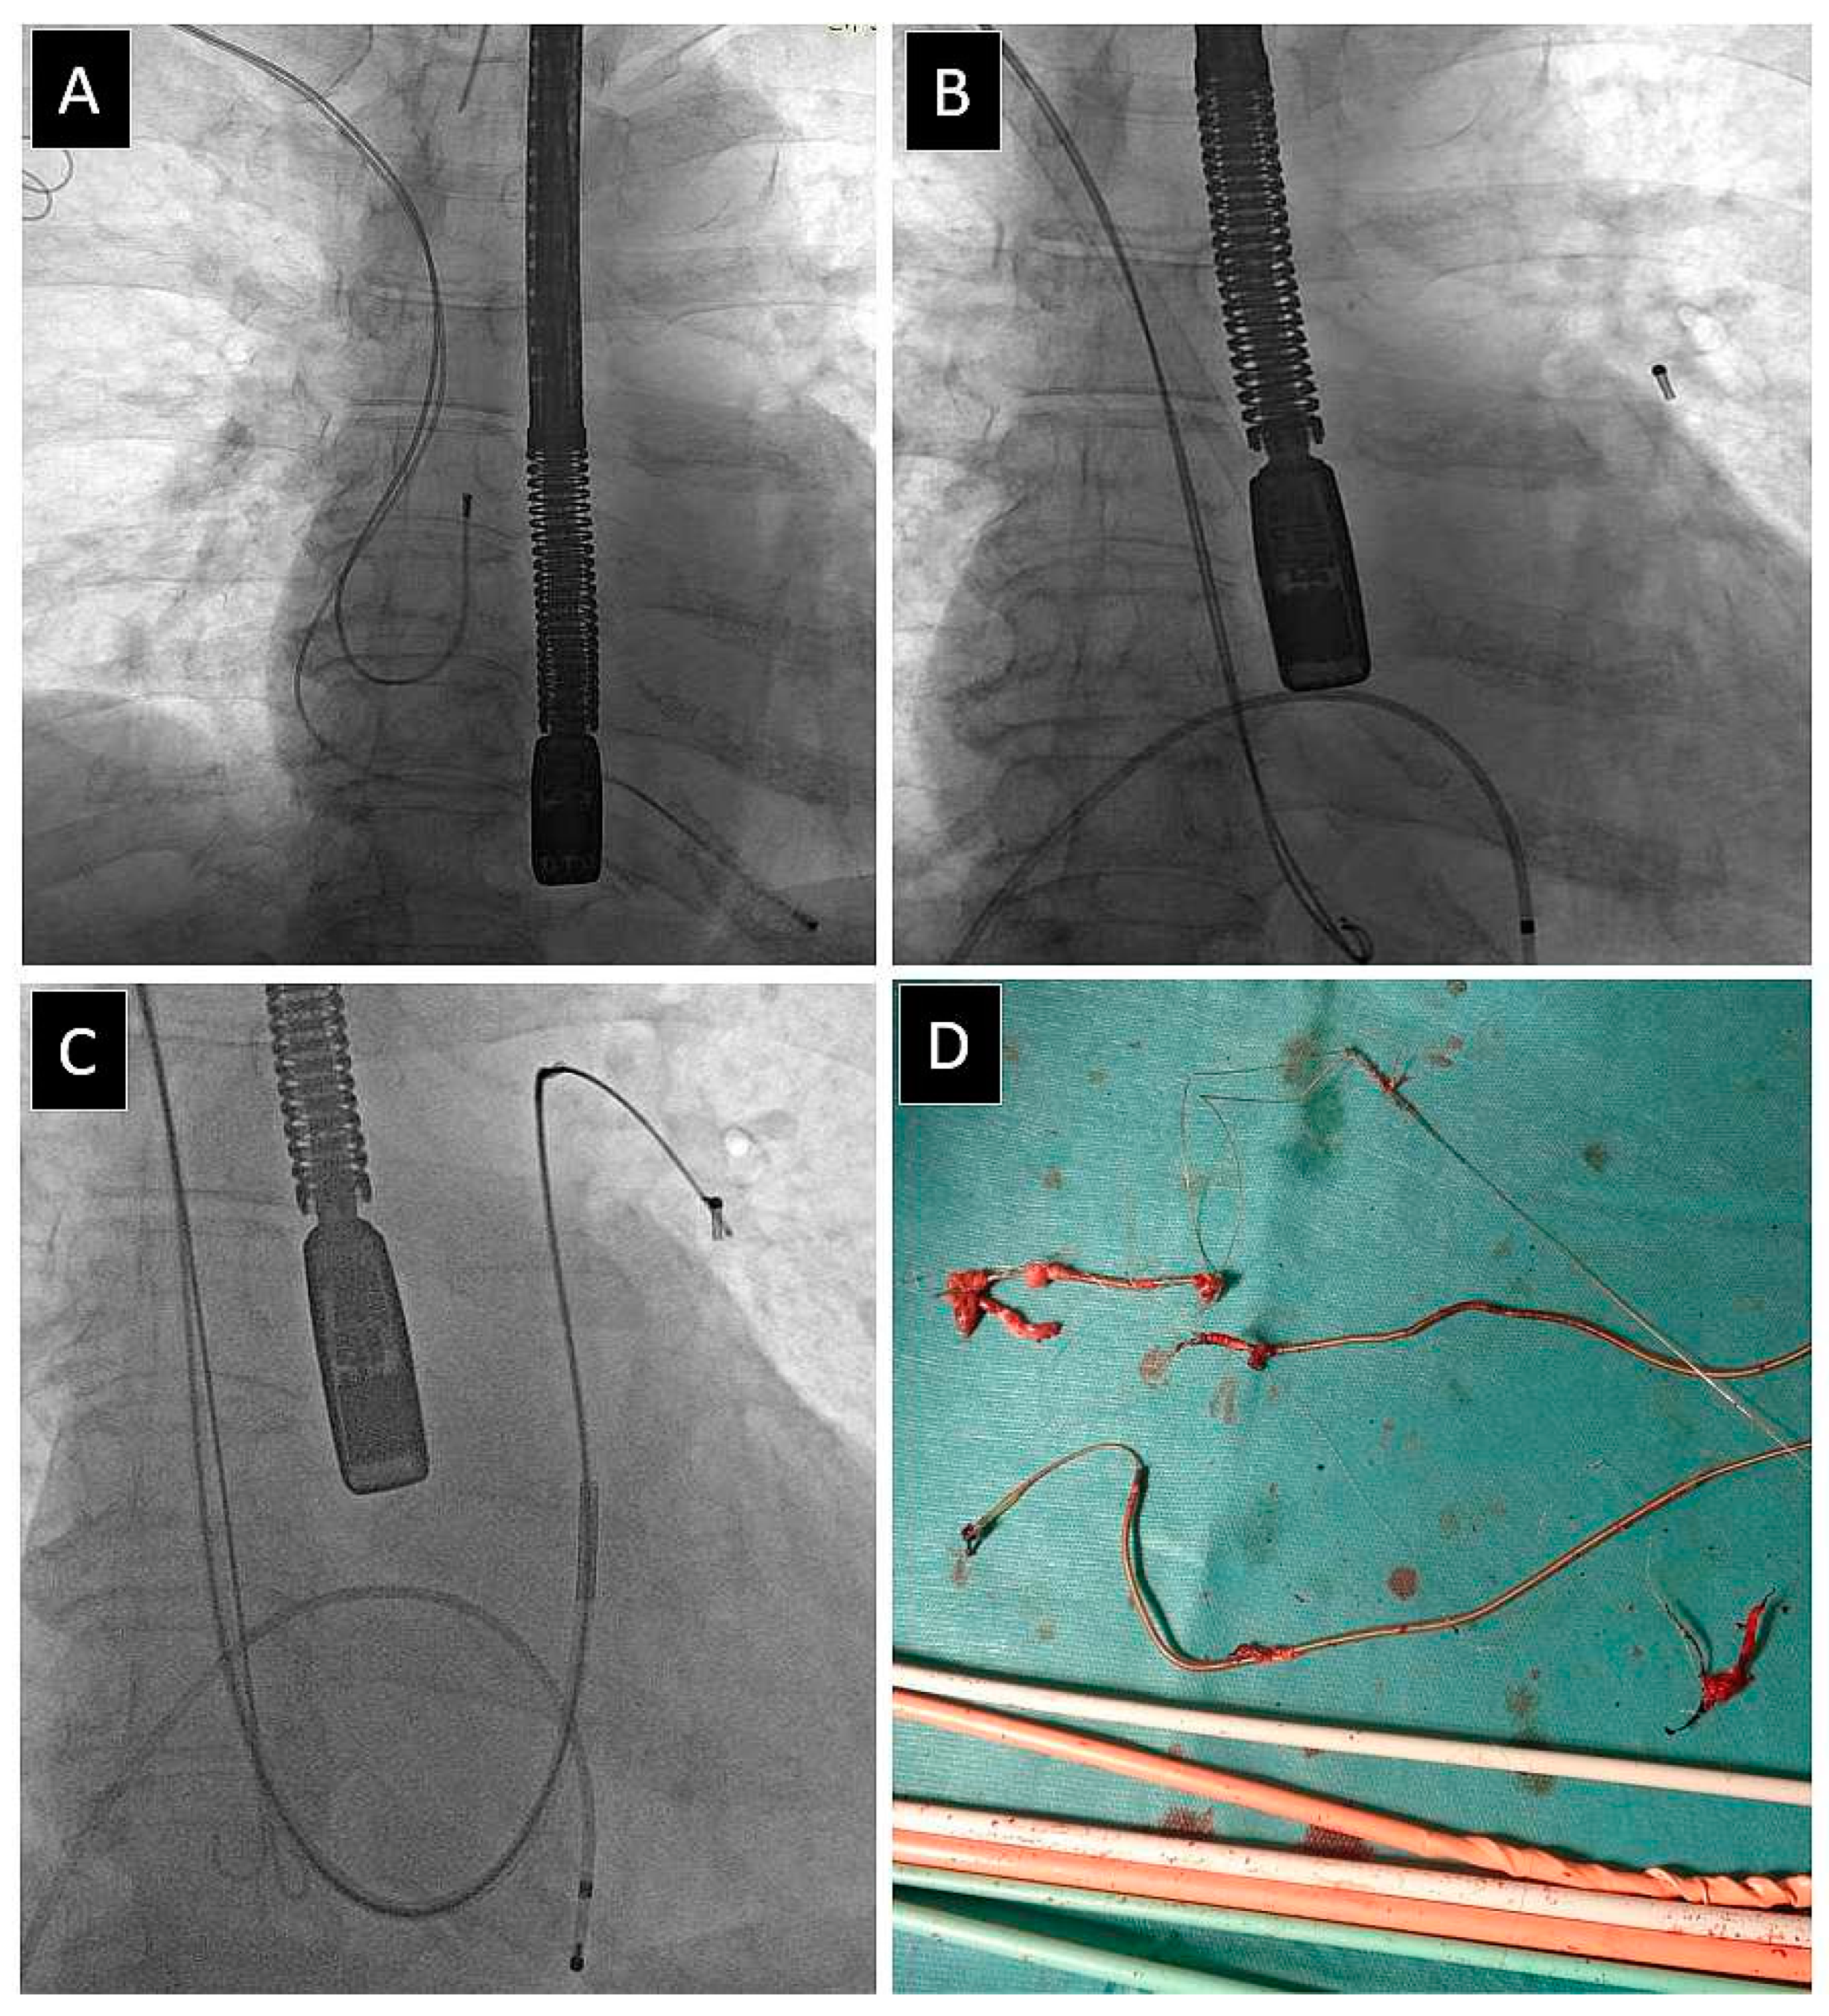

| Use of alternative venous approach * | 122 (3.28) | 63.25 ± 16.30 p = 0.042 | 49.80 ± 18.48 p = 0.001 | 42 (34.43) p = 0.685 | 44 (36.07) p = 0.001 | 53.41 ± 13.61 p = 0.002 | 3.78 ± 3.40 p = 0.003 | 53 (43.44) p = 0.009 |

| Use of alternative venous approach * | 122 (3.28) | 2.66 ± 1.07 p = 0.001 | 28 (22.95) p = 0.001 | 69 (56.56) p = 0.001 | 36 (29.51) p = 0.001 | 3.05 ± 1.63 p = 0.001 | 38 (31.15) p = 0.001 | 40 (32.78) p = 0.001 |

| Use of alternative venous approach * | 122 (3.28) | 2.27 ± 1.15 p = 0.001 | 45 (36.86) p = 0.001 | 12 (54.92) p < 0.001 | 67 (54.92) p = 0.001 | 117 (95.90) p = 0.001 | 161.0 ± 83.89 p = 0.001 | 26.50 ± 18.45 p = 0.001 |

| Use of alternative venous approach * | 122 (3.28) | 79.88 ± 56.65 p = 0.001 | 40.81 ± 33.33 p = 0.001 | 7 (5.74) p = 0.001 | 24 (19.67) p = 0.001 | 50 (40.98) p = 0.001 | 33 (27.05) p = 0.001 |

| Use of alternative venous approach * | 122 (3.28) | 4.81 ± 6.43 p = 0.001 | 65 (53.28) p = 0.001 | 48.37 ± 27.23 p = 0.001 | 3.33 ± 1.01 p = 0.001 | 15.48 ± 7.15 p = 0.001 | 2.39 ± 0.84 p = 0.001 |

| Use of alternative venous approach * | 122 (3.28) | 6 (4.92) p = 0.001 | 5 (4.10) p = 0.008 | 0 (0.00) p = 0.414 | 1 (0.82) p = 0.721 | 4 (3.28) p = 0.085 | 26 (21.31) p = 0.001 |

| Use of alternative venous approach * | 122 (3.28) | 91 (74.59) p = 0.001 | 1 (0.82) p = 0.504 | 0 (0.00) p = 0.708 | 2 (1.64) p = 0.207 | 15 (12.30) p = 0.013 | 59 (48.36) p = 0.762 |